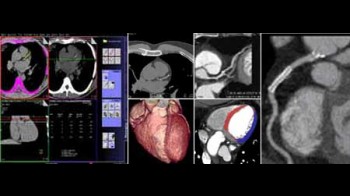

Koronarna CT angiografija

Kardiovaskularne bolesti su ubica broj jedan u današnjem svijetu i odnose svake godine više života nego sve maligne bolesti zajedno. Koronarna bolest je najčešće uzrokovana aterosklerozom (stvaranjem plakova u zidu krvnih žila uzrokojući njihvo suženje). Donedavno, nije postojao neinvazivni način da se direktno analiziraju koronarne arterije na prisustvo aterosklerotskih promjena. Razvoj tehnologije višeslojnog CT-a (MSCT/MDCT) omogućio je detaljno trodimenzionalno prikazivanje kucajućeg srca u toku jednog zadržavanja daha. U našem dijagnostičkom centru nudimo ovu tehniku pregleda koronarnih arterija, na multi-slice aparatu, s najmodernijim softverom i minimalnom dozom zračenja.

Šta je CT koronarografija?

To je metoda prikaza malih arterija koje hrane srčani mišić, upotrebom CT skenera, koji prikazuje protok krvi u koronarnim arterijama i kompjuterskog softvera da bi se dobio odgovarajući trodimenzionalni prikaz. CT angiografija je neinvazivni način da se prikažu zidovi koronarnih arterija I nadju eventualni aterosklerotski plakovi, što pomaže liječniku u odredjivanju rizika srčanog udara.